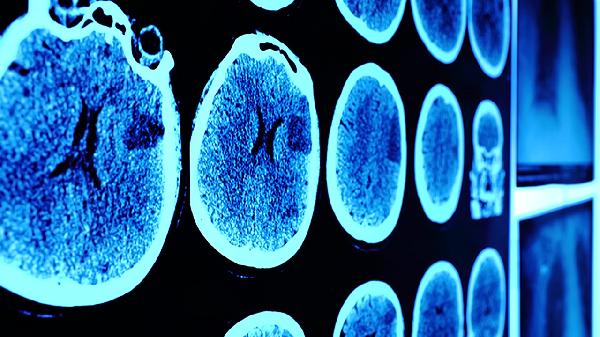

轻度脑震荡可能出现短暂意识丧失,通常不超过30分钟。严重者可能出现嗜睡或难以唤醒。家长需密切观察患儿意识状态,记录清醒时间。若出现持续昏迷、瞳孔不等大等情况,需立即送医进行头颅CT检查排除颅内出血。